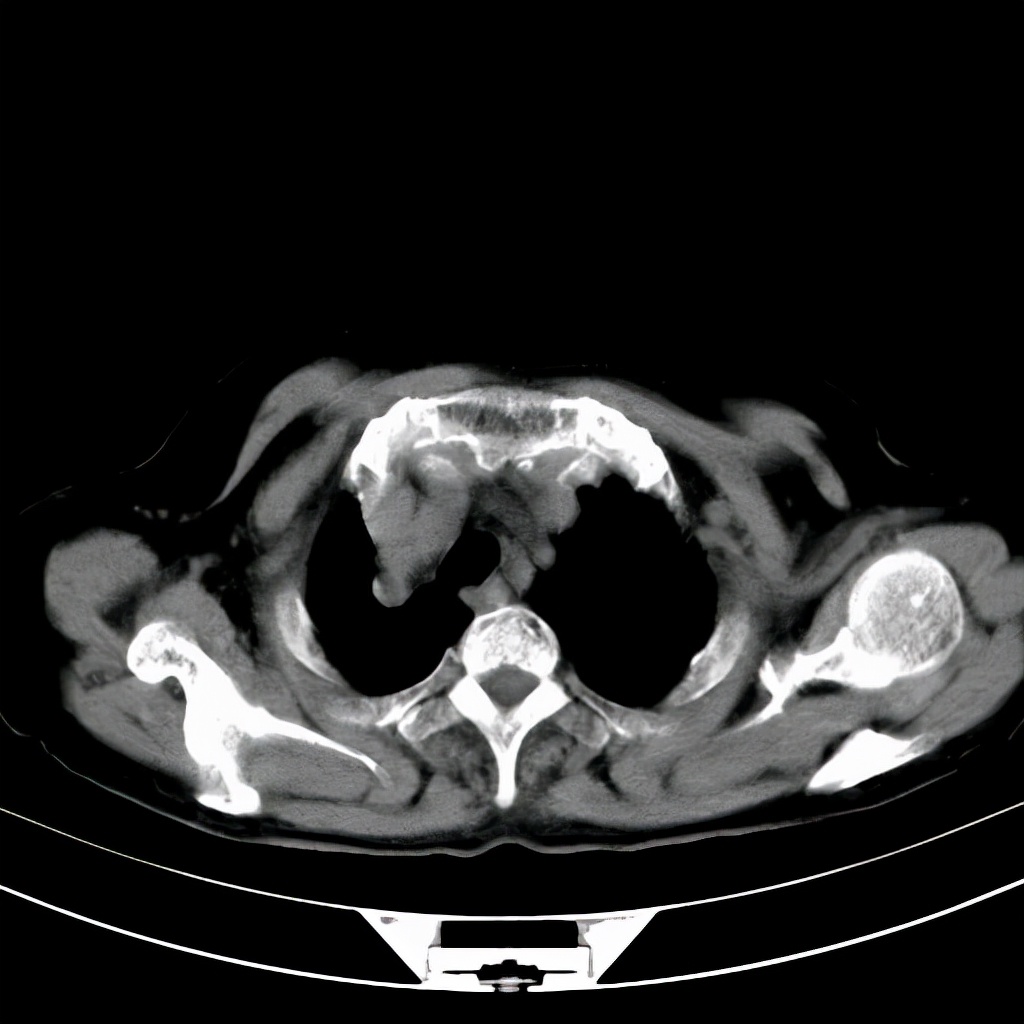

肿瘤